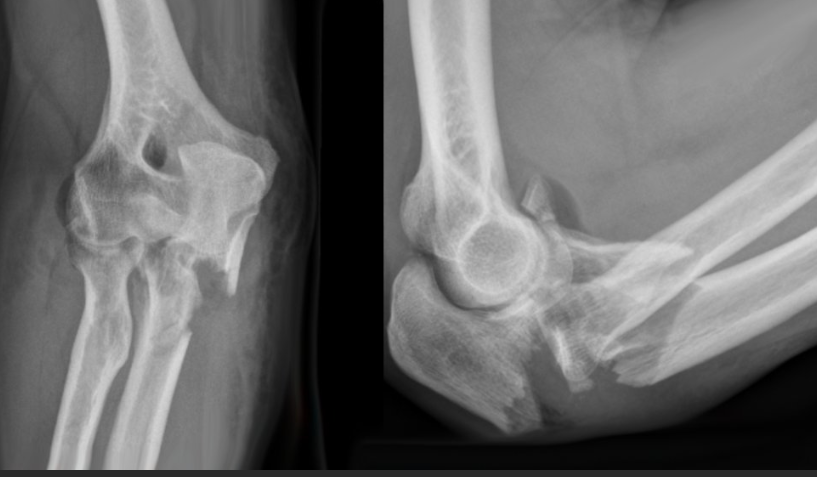

골절:Fractures

설명: 골절은 팔꿈치를 구성하는 뼈 중 하나 이상이 부러지는 것을 의미합니다. 이러한 부상은 주로 낙상이나 직접적인 충격으로 인해 발생합니다.

증상: 극심한 통증, 부종, 변형된 팔꿈치의 모양, 그리고 사용할 수 없는 팔의 기능입니다.

- X-ray (X선): 뼈의 상태를 평가하여 골절이나 관절염 같은 문제를 진단할 수 있습니다.